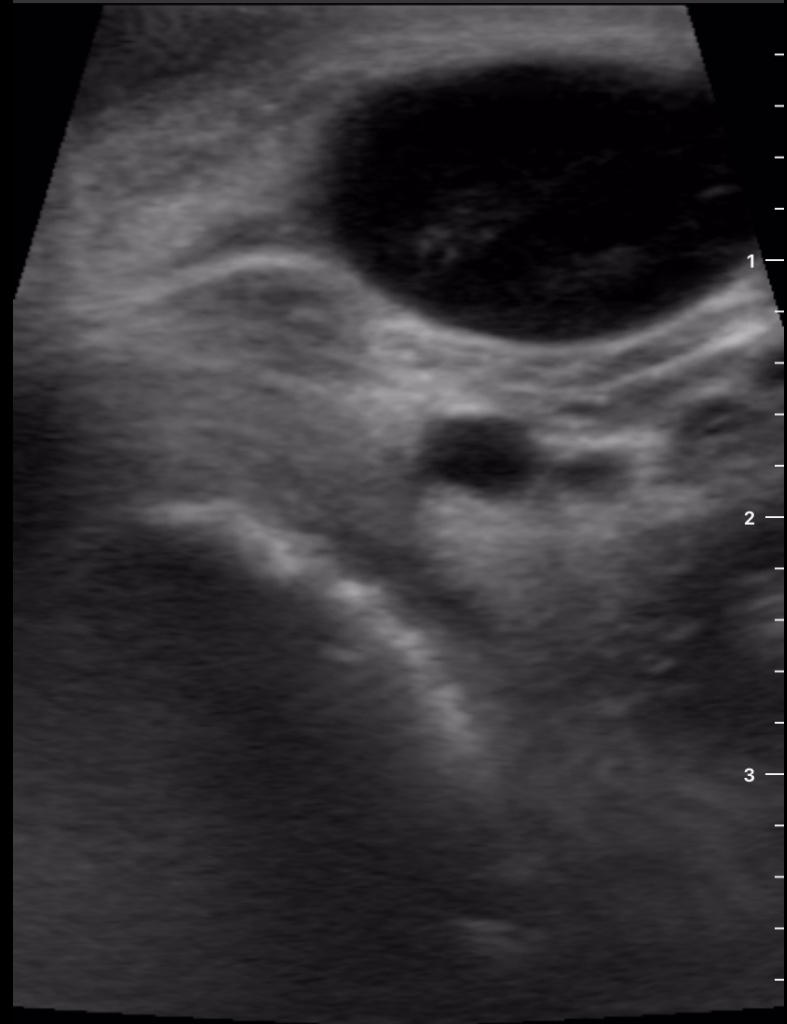

Se decide realizar ecografía clínica con ecógrafo de bolsillo para poder orientar caso, donde se aprecia tumoración de gran tamaño hipoecoica, heterogénea, con calcificaciones de pequeño tamaño en su interior, dependiente de lóbulo tiroideo derecho, sin poder definir límites inferiores, y sin poder localizar la vena cava inferior pero visualizando imagen de vena trombosada junto al istmo.

Ante la sospecha de cáncer de tiroides y la visualización de trombosis venosa que probablemente corresponda a vena cava inferior por la localización se deriva a Urgencias de Hospital de referencia, describiendo hallazgos y sospecha diagnóstica.